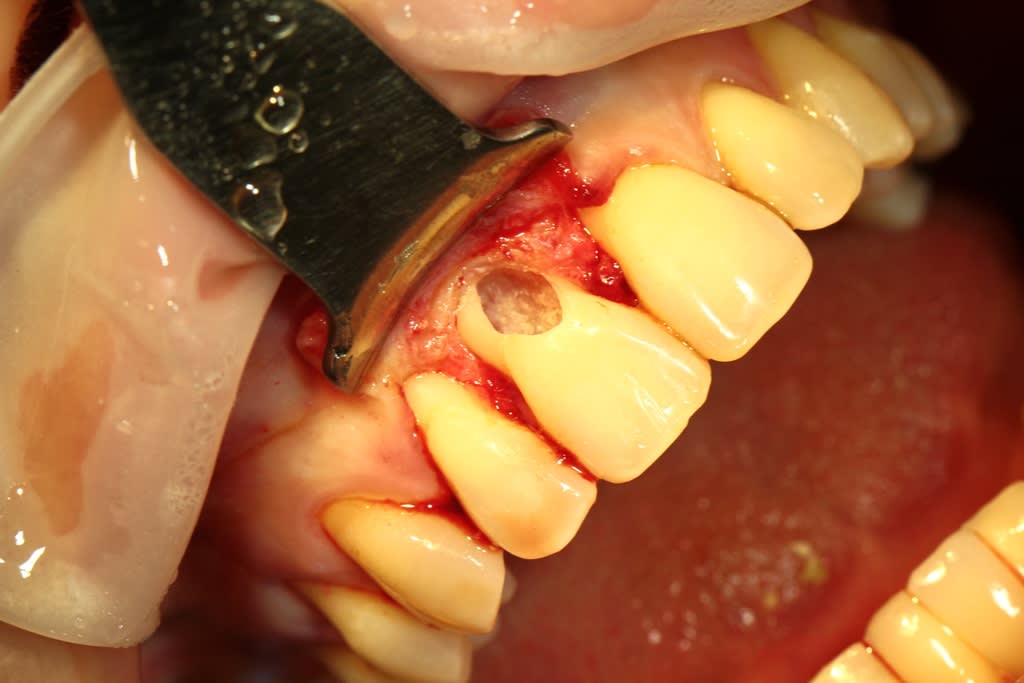

nettoyage et obturation

montmartre écrivait:

> On dirait du matériau de subsitution osseux genre beta tcp, ou me trompe je?

bien vu

je n'avais encore pas de biodentine donc le produit c'est du Vitalos (utilisé en implanto, bitube qui durcissait) qui n'est plus commercialisé depuis 8 ans je crois donc la radio initiale ne date pas de plus de 10 ans mais ça fera 10 ans dans 485 jours... intervention 07/2011) la dernière radio est de la semaine dernière... je n'avais pas revu la patient (qui a donc 48 ans maintenant) depuis 7 ans et honnêtement je pensais qu'elle avait migré ailleurs, et bien non comme tout allait bien, donc pas de contrôle.

le Vitalos n’était pas destiné à cet usage mais j'ai fait une transposition des résultats que j'avais dans d'autres usage.

L’avantage c'est qu'il collait aux parois séchées à la compresse et était biocompatible mais je ne désirait que l'os prenne sa place

Le seul petit défaut sur la dernière radio, c’est la perte osseuse en mésial, par contre la gencive à toujours la bonne hauteur (je n’avais pas fait de décharge latérale, papilles en ½ épaisseur…) et un aspect sympa, dent solide patiente avec un joli sourire

Je ne me la pète pas mais quel plaisir d’avoir eu un succès à 9 ans avec une utilisation "borderline" d'un produit... mon avocat tremble tout les jours :-))